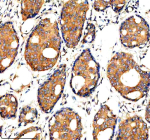

Image R31182 0.5mg/ml if reconstituted with 0.2ml sterile DI water 100 ug 439

Western blot testing of ADAMTS1 antibody; Lane 1: rat liver; 2: (r) heart; 3: (r) brain tissue lysate. Predicted molecular weight 84~120 kDa depending on glycosylation and processing.